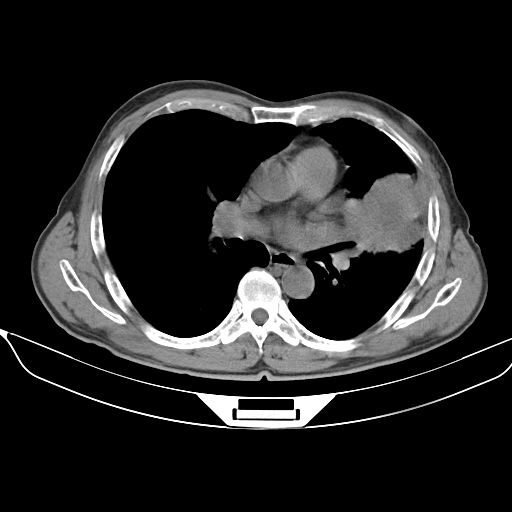

以下是引用shuiyuan在2010-3-1 10:45:00的发言:[br]考虑左肺上叶中心型肺癌伴阻塞型炎症,邻近胸膜受侵。

以下是引用心路寻觅在2010-3-1 10:23:00的发言:[br]1、考虑左肺上叶周围型肺癌[br]2、右上肺陈旧性病灶。[br][br][本贴已被 心路寻觅 于 2010-3-1 10:40:18 修改过]